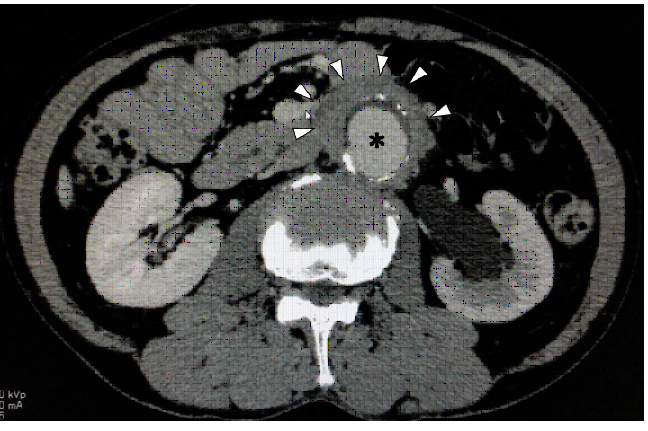

左水腎症を伴う炎症性腹部大動脈瘤の男性(IgG4 165mg/dl)

(※)大動脈(矢頭)大動脈周囲線維化 厚さ12mm